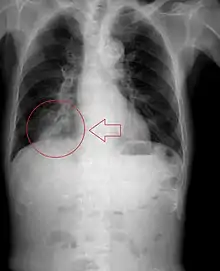

Pulmonary aspiration

Pulmonary aspiration is the entry of material such as pharyngeal secretions, food or drink, or stomach contents from the oropharynx or gastrointestinal tract, into the larynx (voice box) and lower respiratory tract, the portions of the respiratory system from the trachea (windpipe) to the lungs. A person may inhale the material, or it may be delivered into the tracheobronchial tree during positive pressure ventilation. When pulmonary aspiration occurs during eating and drinking, the aspirated material is often colloquially referred to as "going down the wrong pipe".